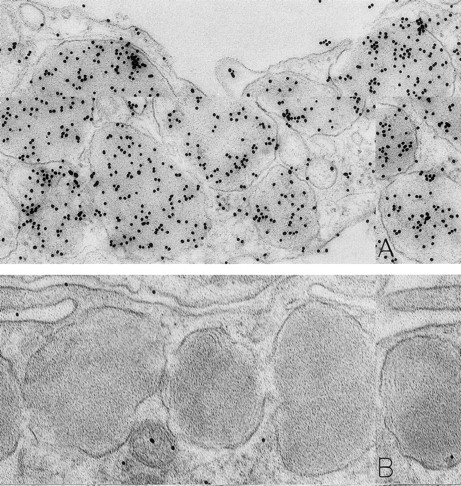

As noted in our previous reports,6 14 ultrastructural evidence of anaphylactic-type degranulation, including the extracellular extrusion of membrane-free cytoplasmic granules, was observed only in biopsies from sites that had been directly injected with rhSCF. Using the DAO-gold enzyme-affinity method, reactivity (gold label) was very strong in the granules of nonsecretory mast cells (in biopsies of either control or rhSCF-injected sites) as well as in any electron-dense cytoplasmic granules remaining in the cytoplasm of skin mast cells that were undergoing secretion (Figs 1, 2, and 3). Moreover, retention of DAO-gold labeling (indicating the presence of histamine) was evident in cytoplasmic granules that exhibited all of the substructural patterns that can be observed in human skin mast cells (Fig 3). Such patterns include granules with crystal (Fig 3A), scroll (Fig 3B), or mixed patterns.

Mast cells in skin biopsies obtained 1 hour 40 minutes (A) or 2 hours (B) after the SC injection of 25 or 5 μg/kg rhSCF, respectively, in patients no. 3 (A) and no. 1 (B), who had received daily SC injections of rhSCF for 13 days. Reactivity for histamine is indicated by DAO-gold labeling in the cytoplasmic granules of a mast cell that exhibits no morphologic evidence of secretory activity (A); DAO-gold label is absent when the grid containing a section of the specimen was digested with DAO before staining with DAO-gold (B). Original magnifications: (A) ×67,500; and (B) ×75,000.

Specificity controls for the histaminase-gold-based affinity technique, including absorption of the DAO-gold reagent by solid-phase histamine before sample staining (Figs 2C and 3C) and digestion of the section with histaminase before DAO-gold staining (Figs 1B and 3D), showed a marked reduction of label or a complete absence of reactivity. In every case tested, there was no staining of sections with colloidal gold alone (data not shown).